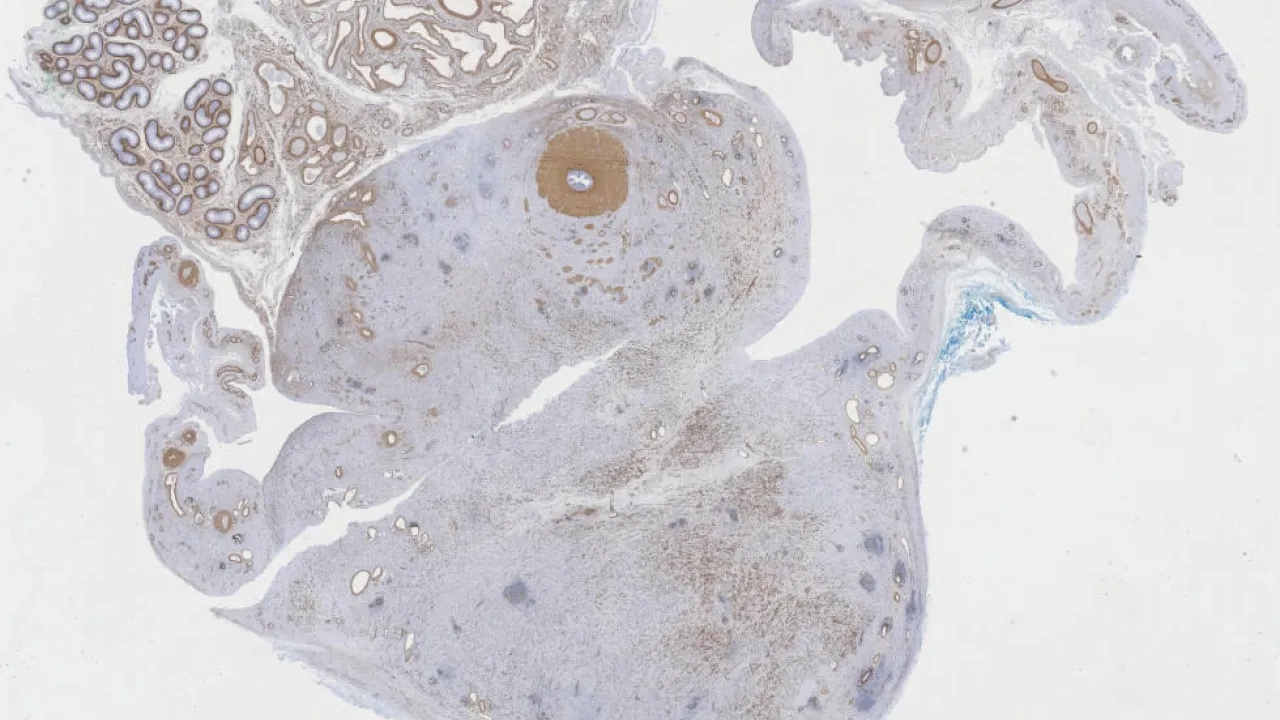

Lymph Nodes, Follicular lymphoma, CD10 stain